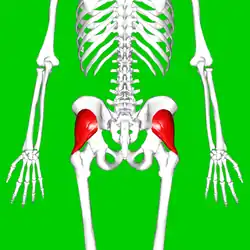

Gluteus minimus muscle (shown in red). Posterior view. | |

Position of gluteus minimus muscle (shown in red). Hip bone is shown in semi-transparent.